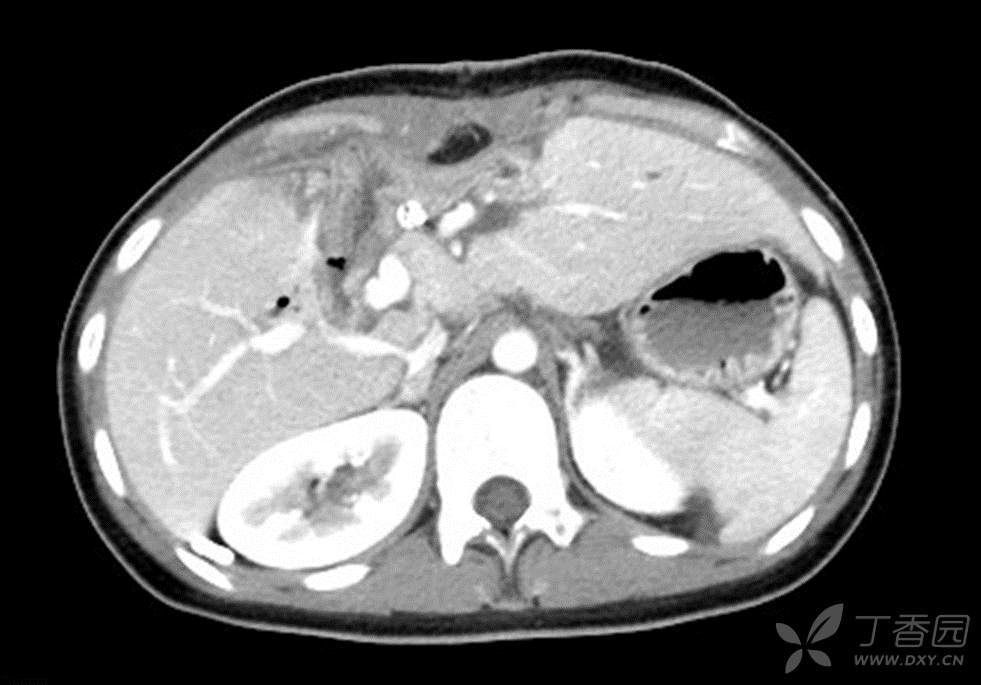

术后恢复顺利,姑娘顺利出院。出院前影像检查如图:

总结:胆总管囊肿不是一个简单的病,即使是最常见的Todani-I型,也有很多人因为不彻底,术后反复发烧。而再次手术因腹腔内粘连,难度进一步加大。作为一个良性病,术者承担的压力更大,要保证安全性,又要保证彻底性,应当予以十二分的重视才对。